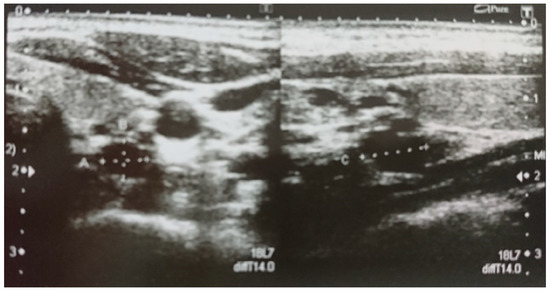

2. Case Presentation

2.1. Patient’s Description